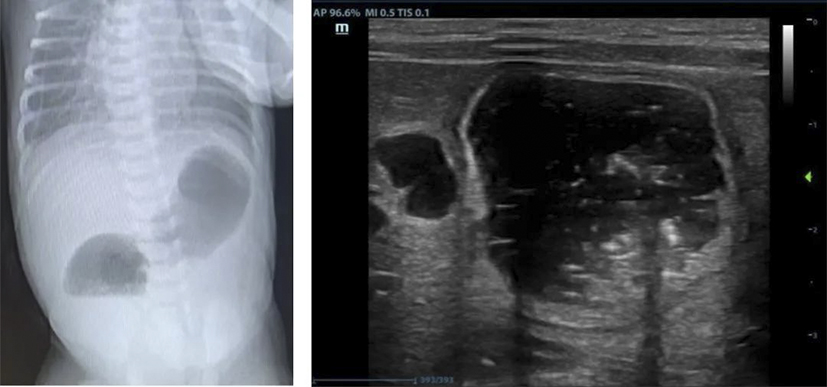

該患兒母親孕期產(chǎn)檢中四維彩超提示胎兒十二指腸狹窄或閉鎖可能,一直在我院產(chǎn)科、超聲科、小兒外科的MDT團(tuán)隊(duì)門診隨訪監(jiān)測(cè),直至足月后剖宮產(chǎn)娩出。嬰兒轉(zhuǎn)至新生兒科進(jìn)一步完善超聲、消化道造影明確診斷為十二指腸閉鎖,急需手術(shù)治療。

十二指腸閉鎖是一種先天性消化道畸形,發(fā)病率約1/50000至1/10000,占所有腸閉鎖的50%以上,約30%合并唐氏綜合征,也可能伴隨其他先天異常(如心臟畸形、腸旋轉(zhuǎn)不良等)。產(chǎn)前主要表現(xiàn)為母體羊水過多,超聲可見胃和十二指腸近端擴(kuò)張(“雙泡征”)。出生后表現(xiàn)為24-48小時(shí)內(nèi)嘔吐、上腹部膨隆、排便減少或無胎糞排出等。通過產(chǎn)前超聲、出生后X線檢查可以明確診斷,手術(shù)是唯一的治療方法。微創(chuàng)腹腔鏡手術(shù)具有創(chuàng)傷小、出血少、術(shù)后恢復(fù)快、縮短住院時(shí)間等優(yōu)勢(shì),目前已廣泛應(yīng)用于十二指腸閉鎖的治療。